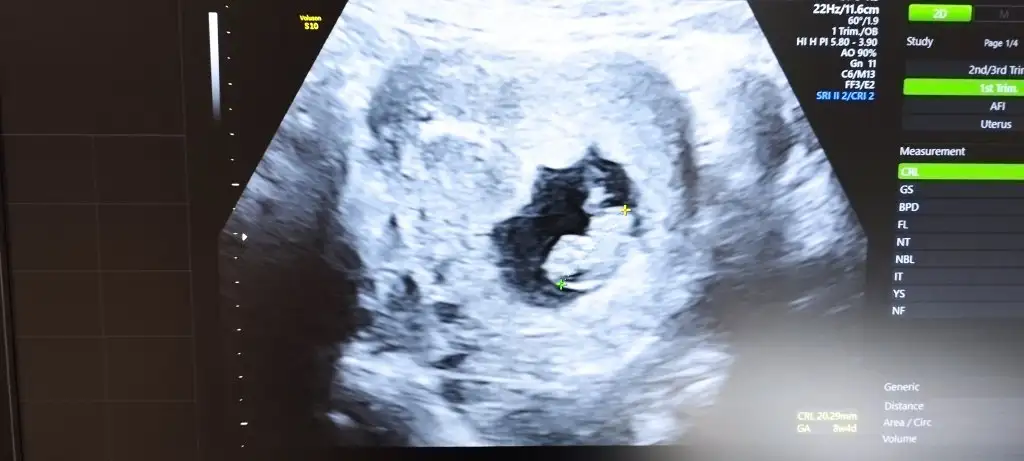

• IMG_20221026_094938.webp

IMG_20221026_094938.webp

24 KB · Görüntüleme: 46

• IMG_20221026_094924.webp

IMG_20221026_094924.webp

21,6 KB · Görüntüleme: 34

• IMG_20221026_094919.webp

IMG_20221026_094919.webp

32,2 KB · Görüntüleme: 39